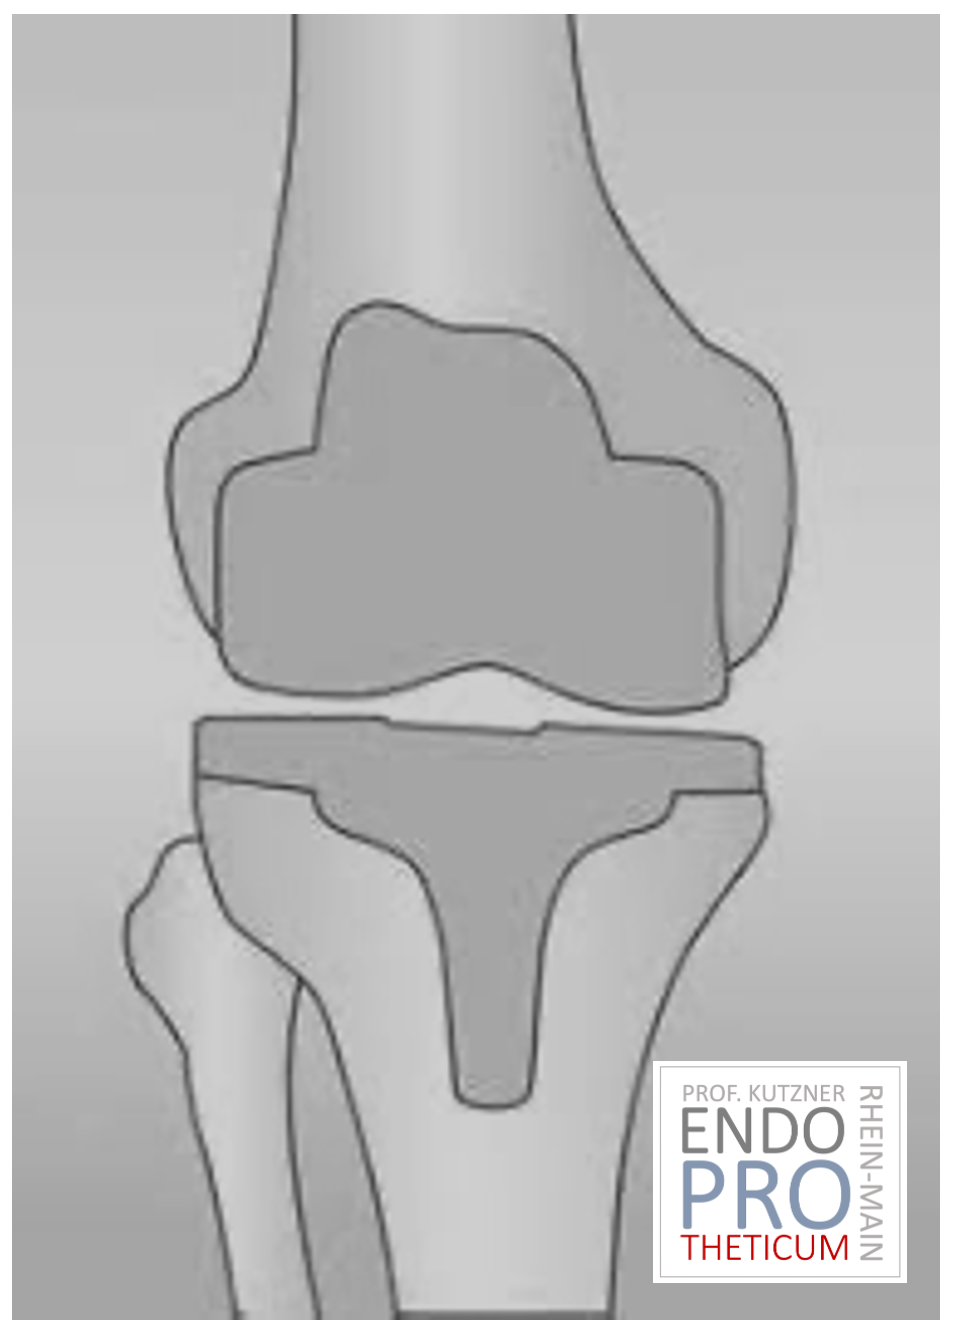

SURFACE REPLACEMENT

TKA (ARTIFICIAL KNEE JOINT)

The artificial knee joint replaces the cartilage surface that has been destroyed by osteoarthritis.

The underlying bone on the femur and tibial head remains intact. Some compare a modern artificial knee joint to a crowning of a tooth; the exact term is the so-called

bicondylar resurfacing. Between the new surfaces on the upper and lower leg is the so-called inlay made of a specially hardened white plastic, which can be seen in the X-ray image as the distance between the metal parts.